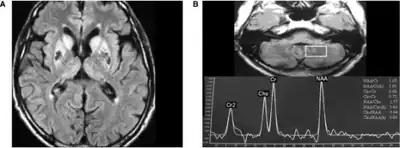

Neuroimaging

Neuroferritinopathy is most commonly diagnosed using MRI and other neuroimaging techniques.[1] MRIs help identify the iron deposits in the cerebellum, basal ganglia, and motor cortex common to neuroferritinopathy.[8] MRIs of affected individuals also show mild cerebellar and cerebral atrophy, or tissue breakdown, and gas cavity formation in the putamen.[8] Most importantly, the MRIs show misfolded ferritin proteins and iron deposits in the glial cells of the caudate, putamen, globus pallidus, cerebral cortex, thalamus, and purkinje cells, causing neuronal death in these areas.[8]